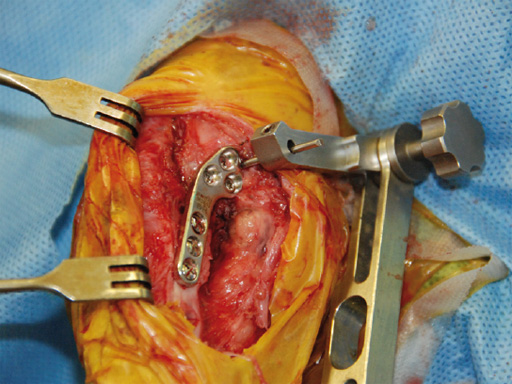

An 11-year-old female, spayed, 13.6 kg cocker spaniel had a complete tear of the left cranial cruciate ligament. A 2.4 mm TPLO plate was perfect for this dog due to the excessive slope of the tibial plateau (30) and the size of the dog. Three 2.4 mm locking screws were used proximally and three 2.4 mm cortical screws were used distally. The contour of this plate matches the contour of the bone almost perfectly. The plate is also designed to optimize the angle of the proximal screws so that they engage the most dense and thickest bone and avoids penetration of the stifle joint.